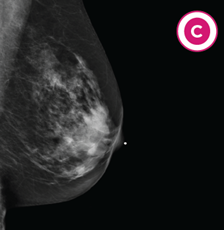

C. Heterogeneously (het-er-uh-jee-nee-uhs-lee)